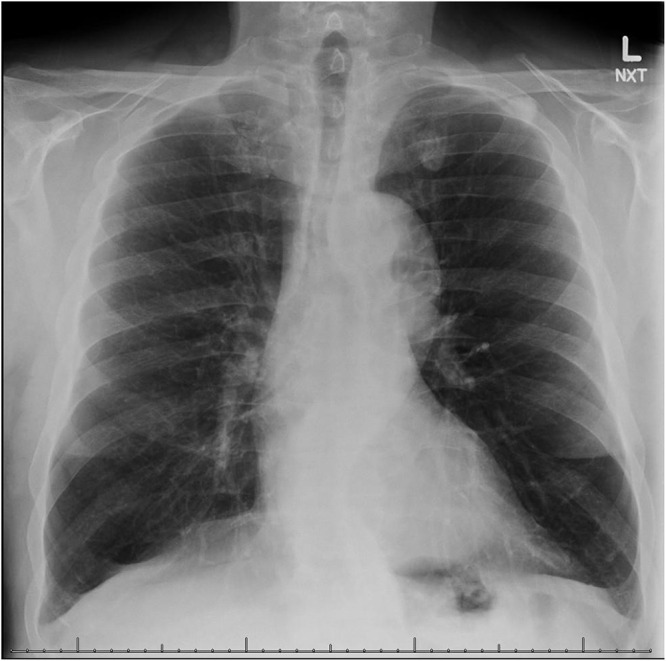

随着越来越多的州和国家将大麻用于医疗和娱乐用途合法化,吸食大麻在美国和世界上变得越来越普遍。大麻烟雾中的许多致癌物与烟草烟雾中的致癌物相似,但在文献中很难找到大麻吸烟与慢性阻塞性肺病(COPD)之间的因果关系。我们报告一位患者,其肺气肿的主要危险因素是每日吸食大麻超过35年,没有个人吸烟史,也没有其他明显的危险因素。目前的研究表明,慢性大麻吸烟与各种肺部疾患、1秒用力呼气量(FEV1)与用力肺活量(FVC)之比有关,但与慢性支气管炎不一致。有了这个病例,我们增加了目前的文献,表明长期大量使用大麻和慢性阻塞性肺病之间可能存在关系。

Marijuana smoking has become increasingly common in the United States and the world as more states and countries have legalized it for medical and recreational use. There are a number of carcinogens in marijuana smoke similar to those in tobacco smoke, and yet it has been difficult in the literature to find a causal relationship between marijuana smoking and chronic obstructive pulmonary disease (COPD). We present a patient whose main risk factor for emphysema is daily marijuana smoking for upwards of 35 years with no personal history of smoking tobacco, and no other obvious risk factors. Current studies have shown association with chronic marijuana smoking and various lung complaints, forced expiratory volume in 1 second (FEV1) to forced vital capacity (FVC) ratio, and inconsistently with chronic bronchitis. With this case, we add to the current body of literature that suggests a possible relationship between long-term, heavy marijuana use and COPD.